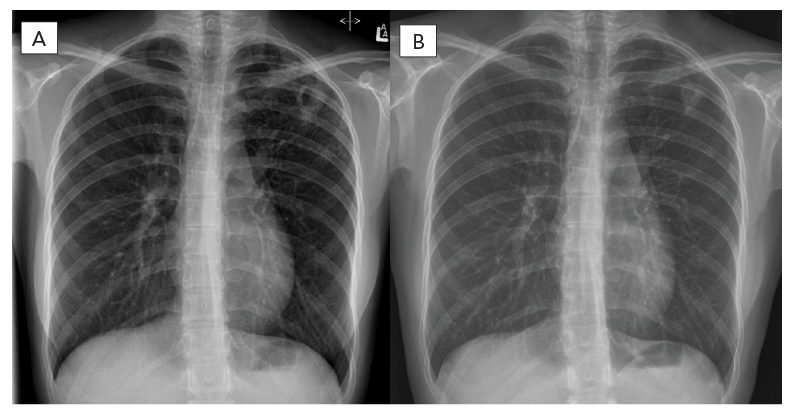

In March 2021, an 18-year-old female was referred to a provincial TB program with a five-month history of cough and several weeks of night sweats. Chest radiograph revealed left upper lobe cavitation (Figure 1). Sputum samples demonstrated acid-fast bacilli on smear, which was confirmed as Mycobacterium tuberculosis complex by polymerase chain reaction assay targeting the IS6110 and mpt64 genes. The patient was born in China and had moved to Canada three years prior to her TB diagnosis. She had no known prior TB exposure or treatment, was a non-smoker and was on no medications. Baseline investigations were negative for human immunodeficiency virus, hepatitis B/C and diabetes.

Figure 1 - Text description

The left X-ray showing left upper lung thick walled cavitary lesion pre-treatment with the right X-ray showing improvement on follow-up six-months post completion of treatment.

One month after hospitalization and treatment optimization, all TB symptoms had resolved and sputum smears and cultures were consistently negative. Serial follow-up chest imaging demonstrated improvement. In November 2021, BPaL regimen treatment was stopped. More than six months post treatment the patient remained symptom free with negative sputum cultures and improved chest imaging (Figure 2 and Figure 3).